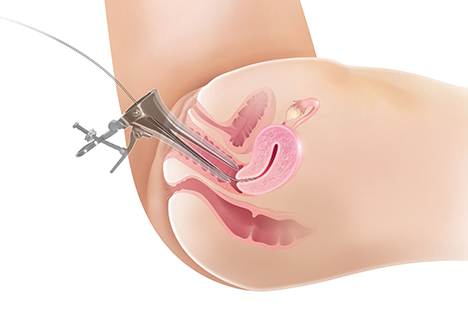

リピオドール®を使用した子宮卵管造影(HSG)の手順

提供: Dr. Kim Dreyer, Amsterdam University Medical Center (Netherlands)